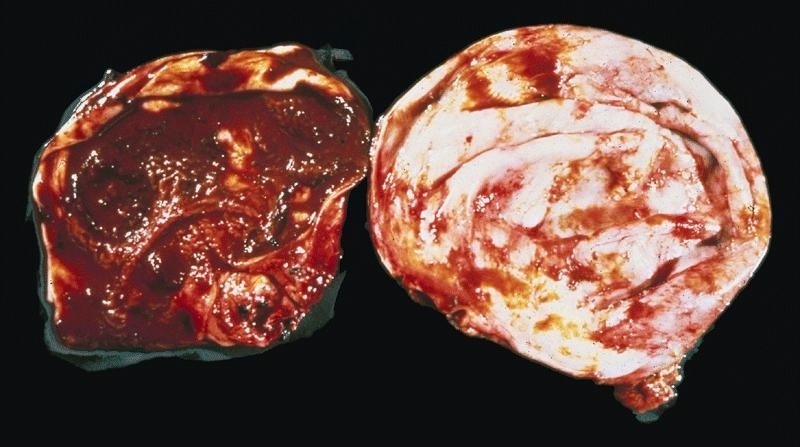

Gross description

- Ovarian endometriotic cysts (endometriomas) have fibrotic walls, a smooth lining and dark brown cyst contents (chocolate cyst), often adherent to adjacent organs

- Polypoid endometriosis has a polypoid configuration that raises the differential diagnosis of a neoplasm on gross and intraoperative examination (Am J Surg Pathol 2004;28:285)

- Red, brown, white plaques, sometimes with a gelatinous appearance (Arch Gynecol Obstet 2015;292:1295, Taiwan J Obstet Gynecol 2019;58:328)

Gross images